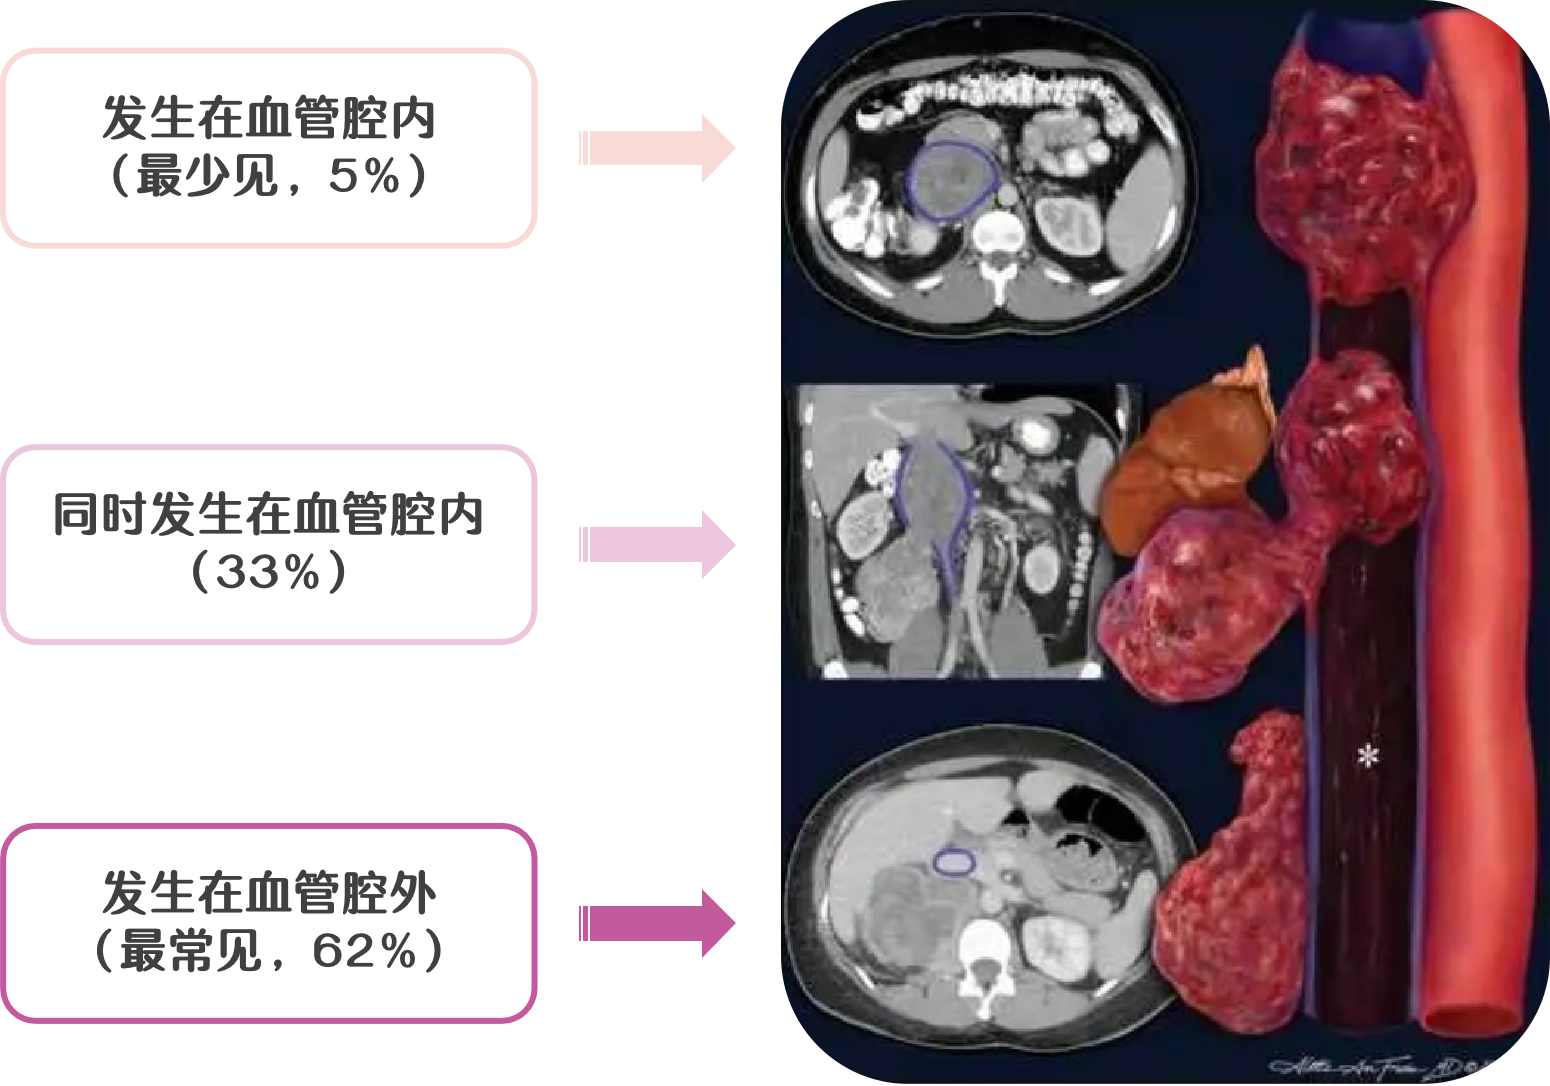

腹膜后平滑肌肉瘤的生长方式主要有三种:① 完全长在血管外,最常见(62%);② 完全长在血管内,最少见(5% );③ 同时长在血管内外 (33%)。

9a0ccceeef94130db73768fa4105b91c.png 图 29:平滑肌肉瘤与血管腔的关系示意图

2f530b96476cae13672532ff0a7ab285.png 图 30:平滑肌肉瘤的三种生长方式(① 血管腔内;② 血管内外;③ 血管腔外)